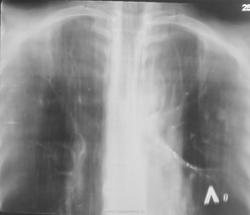

Договорена консультация и госпитализация в ОПТД. По просьбе коллеги фтизиатра делам томограммы в прямой проекции.

Пациента довольно успешно лечили по поводу "пневмонии", да и субъективно пациент отмечал улучшение, НО перед выпиской, ВДРУГ, при микроскопии были обнаружены МБТ.

Вы правы коллега! По всей видимости, "содружественная патология" выплывет...

Госпитализирован в ОПТД. Проводится специфическое лечение, но ВИЧ выявлен не был.

Динамика в процессе лечения.